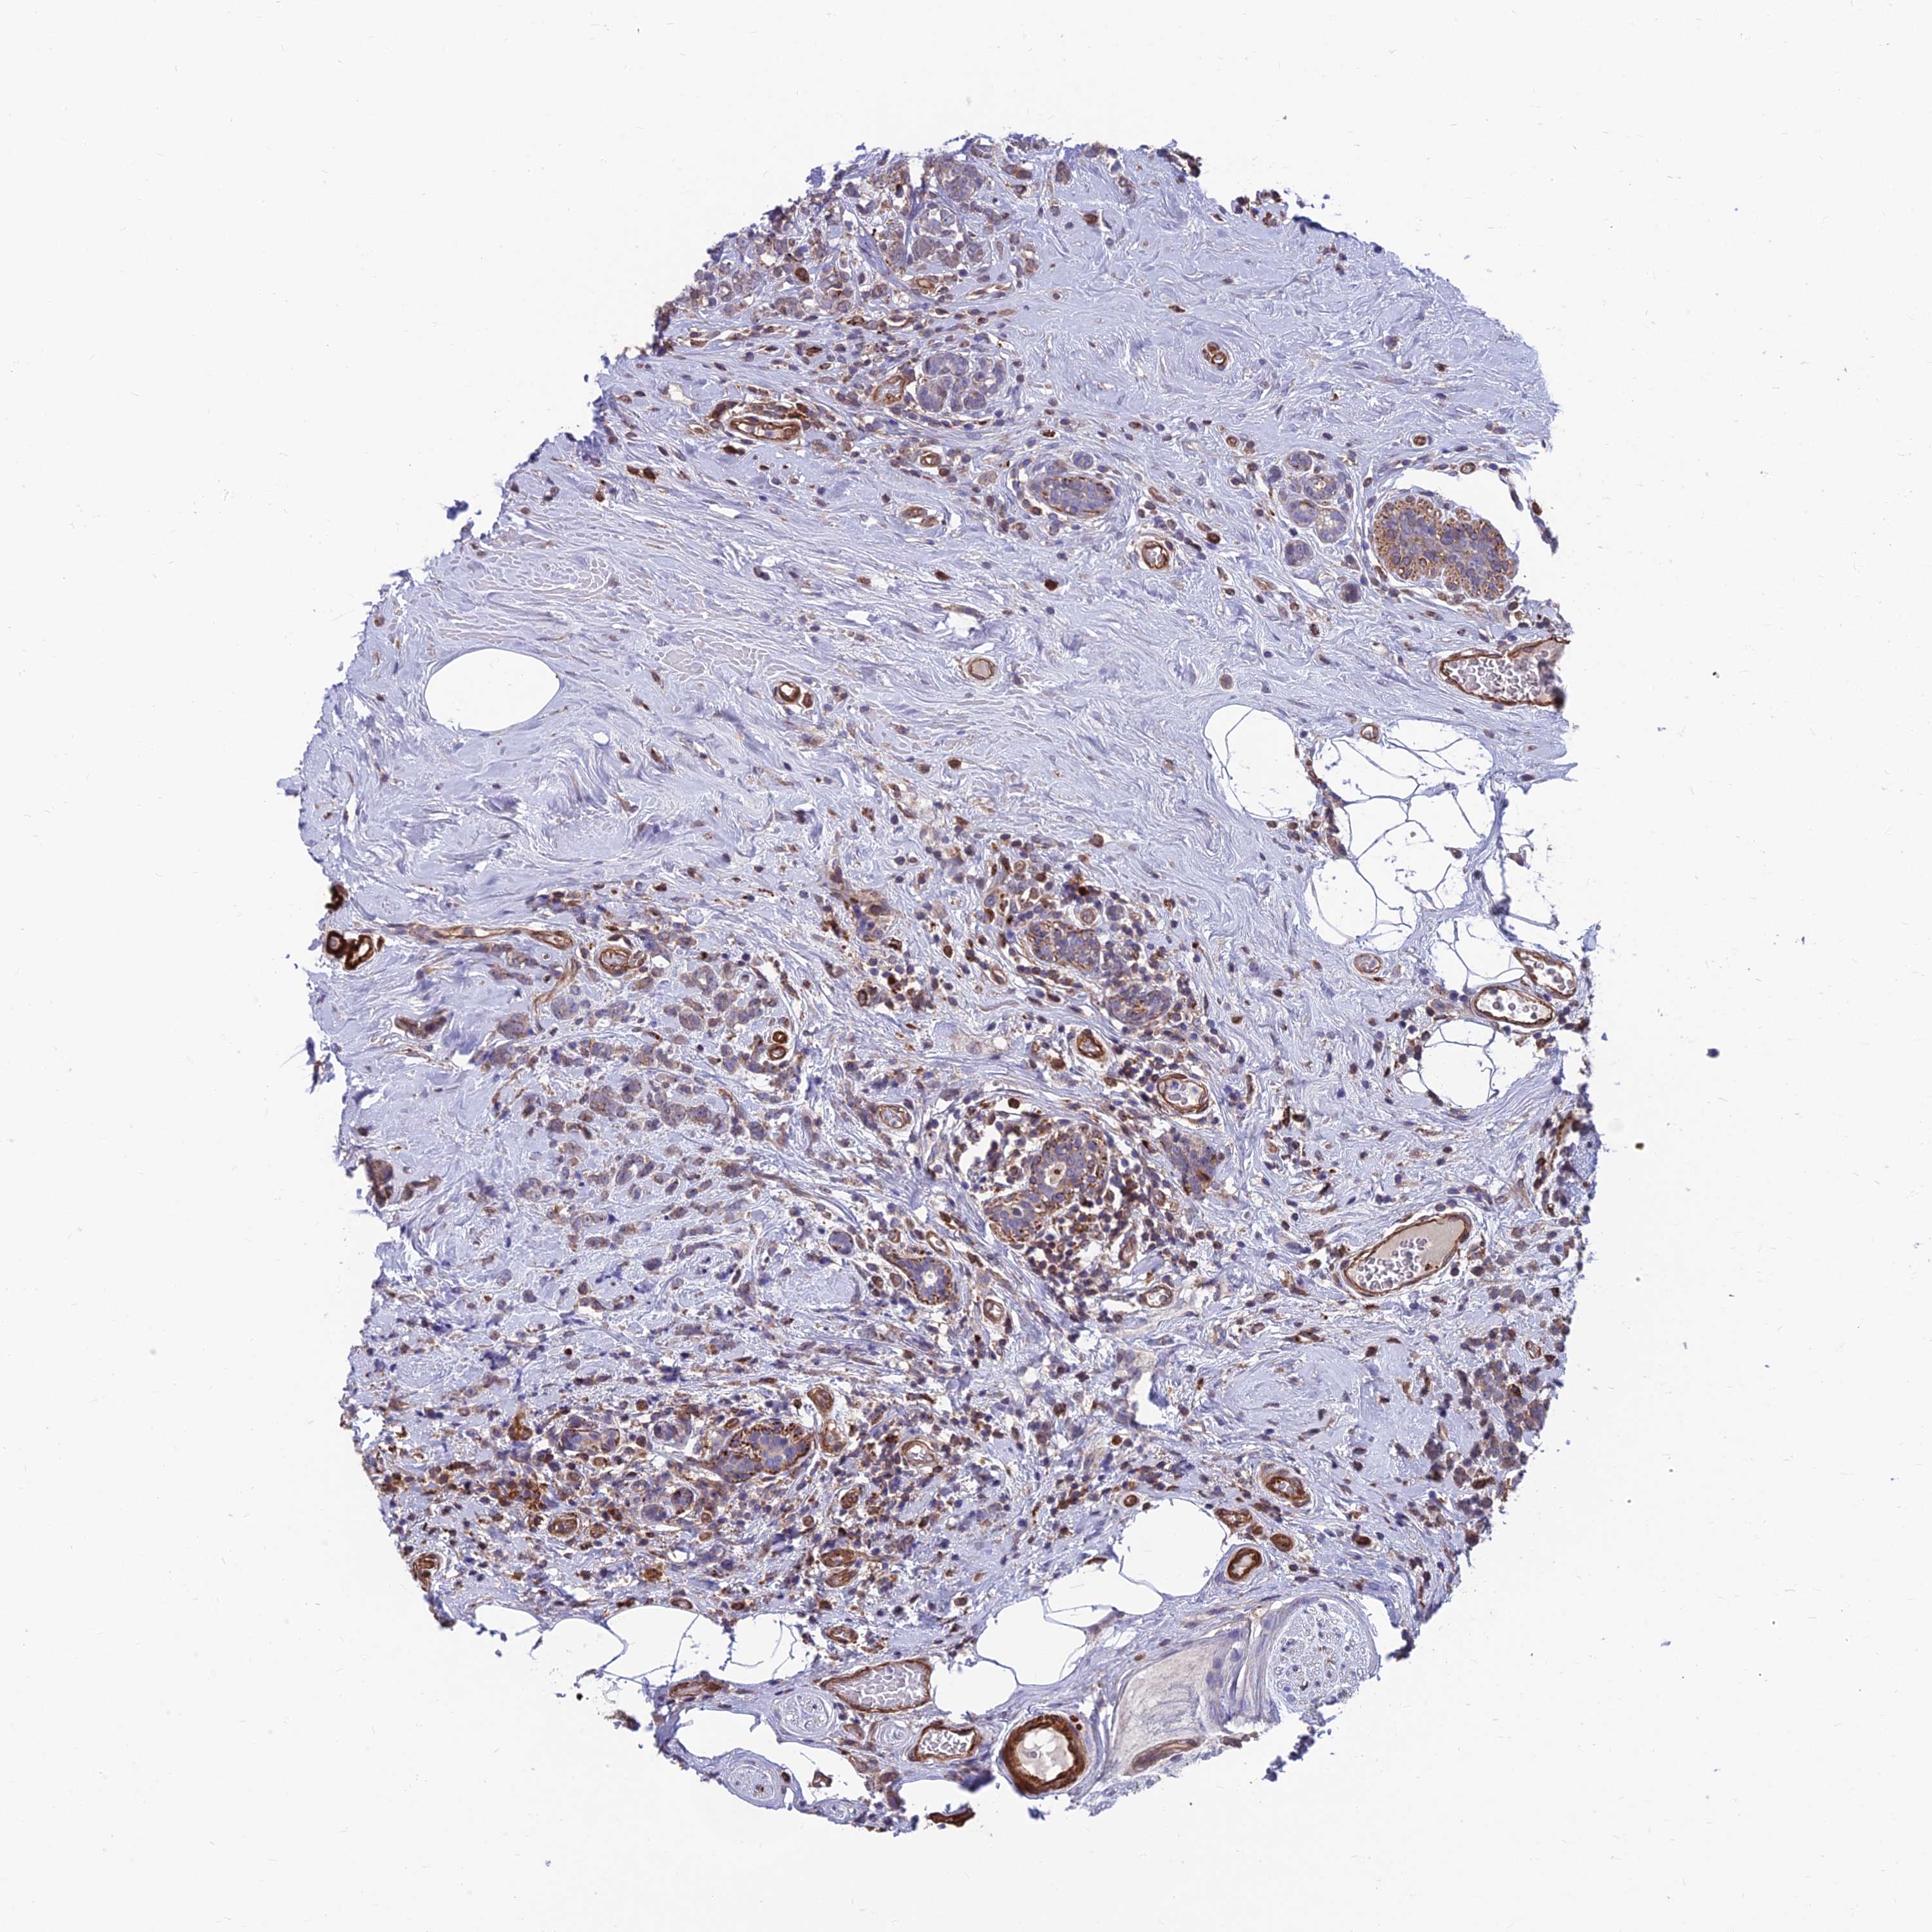

CANCER BREAST CANCER Show tissue menu

BRCA TCGA BRCA VALIDATION PROTEIN EXPRESSION